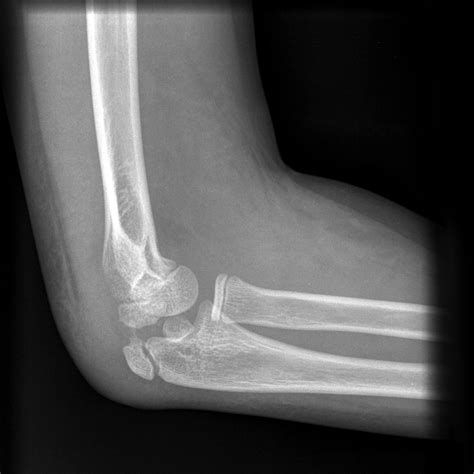

Doctors will typically use X-rays to visualize the bones and confirm a diagnosis. In more complex cases, such as intra-articular fractures, a CT scan might be required to determine if surgical intervention is necessary to realign the bone fragments.

- broken elbow pictures